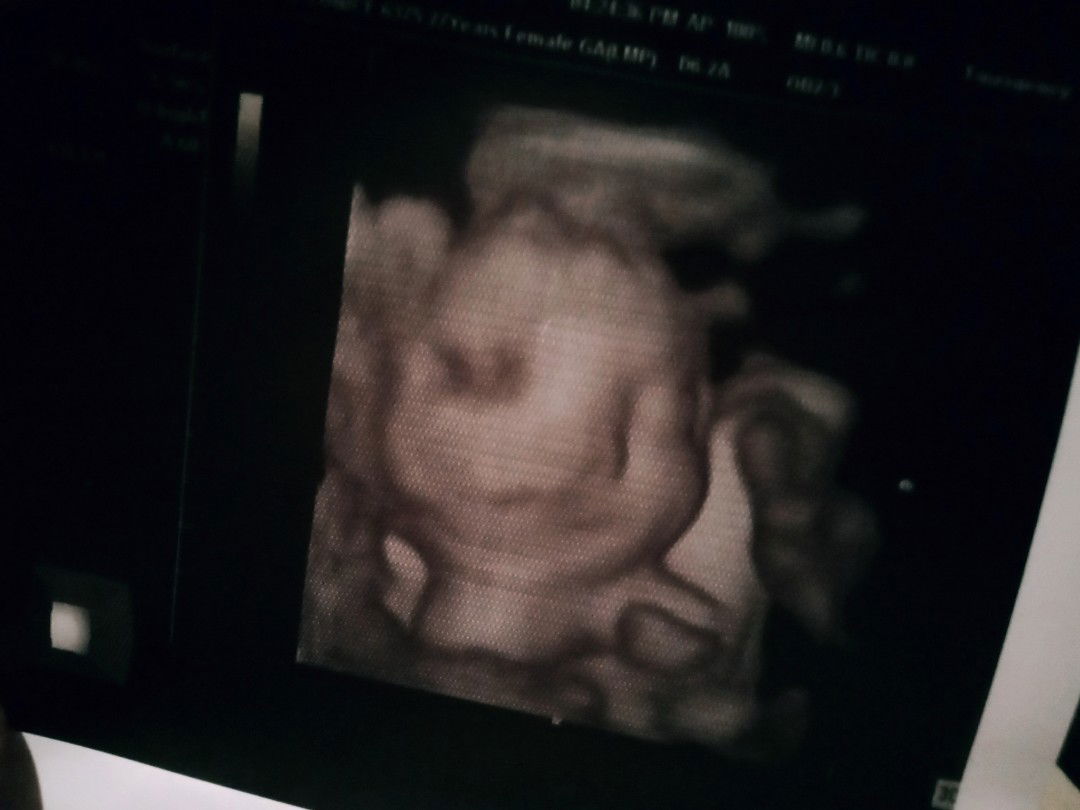

Humanoids, meet my daughter, Lora Jennise. :)

Sa wakas anak! After 3 days na pabalik-balik, pagyugyog ng bongga sa tummy ko, pagkain ng mga matatamis at pag-inom ng malamig na tubig, woooh! pinakita mo na rin ang face mo! Masyado ka kasing mahiyain eh, mana ka saken. ???? Grabe ka naman anak, nawala ang pagod at sama ng pakiramdam ko nang masilayan ko na sa unang pagkakataon ang maganda mong mukha! Sobrang nakakainlove ka anak. Tabatabachingching ka rin katulad ni mama.?? (Buti at binigyan ako ng sample pic mo baby kahit malabo pa, kasi 5 days pa ibibigay yung pics and vids mo eh. I can't wait kasi talaga na. ??? Nakakagigil ka anak! ??) Mahal na mahal ka namin. ? Thank you talaga Lord sa biyaya mong ito! ? See you soon, my love. ??